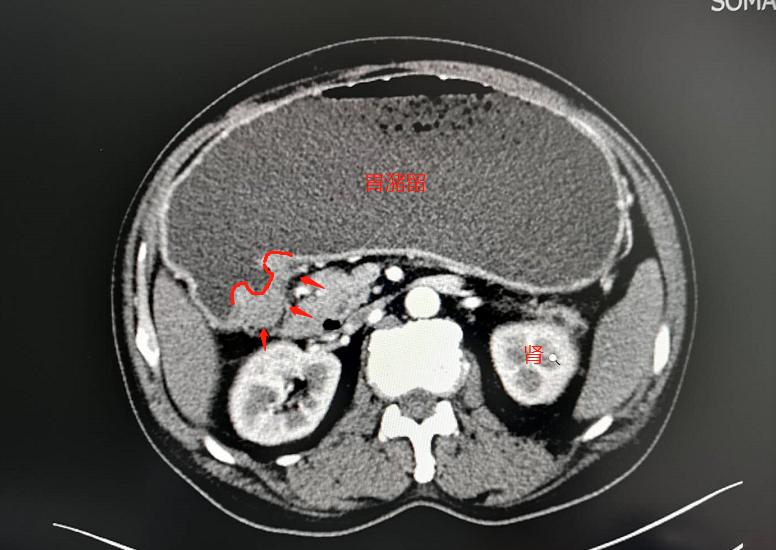

急诊CT显示胃里满满的酒液和食物渣,同时胃小弯背侧的胃壁增厚,超过1厘米,内侧面可见一个火山口状(红线)改变,说明这里的胃壁破溃、脱落,烂了一个很深的溃疡。

这是典型的溃疡型胃癌表现。

赶紧住院,胃肠减压,做胃镜,病理中低分化胃腺癌。